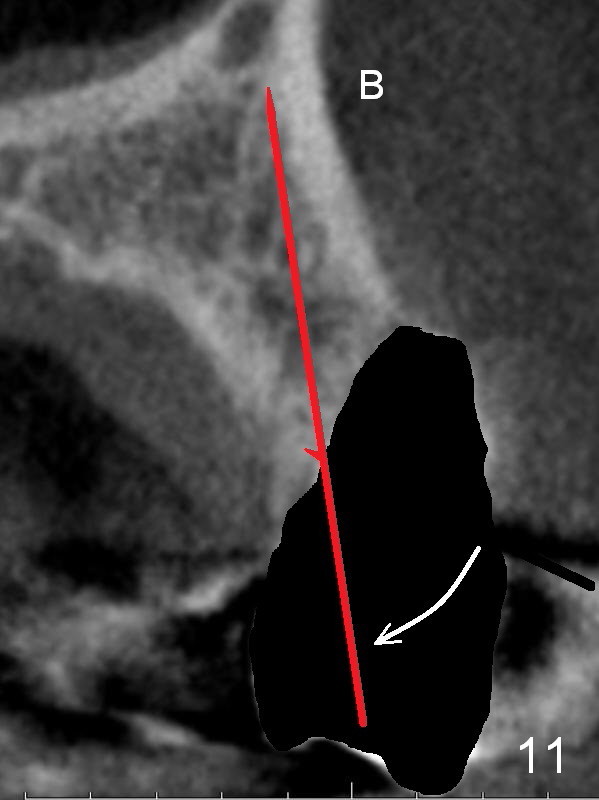

After extraction, the bottom of the socket must be oblique (Fig.9 arrowheads). As usual, osteotomy is initially at the junction of palatal (Fig.10 P) 1/3 and middle 1/3 perpendicular to the plate. Once the drill gets engaged, the trajectory is to be changed (Fig.11 curved arrow) so that the apical end of the osteotomy (red line) is as close to the buccal plate (B) as possible. The purpose is to keep the palatal end of the osteotomy as palatal as possible. In spite of the effort, an angled abutment is expected, as large as 20 degree (Fig.8 purple angle).